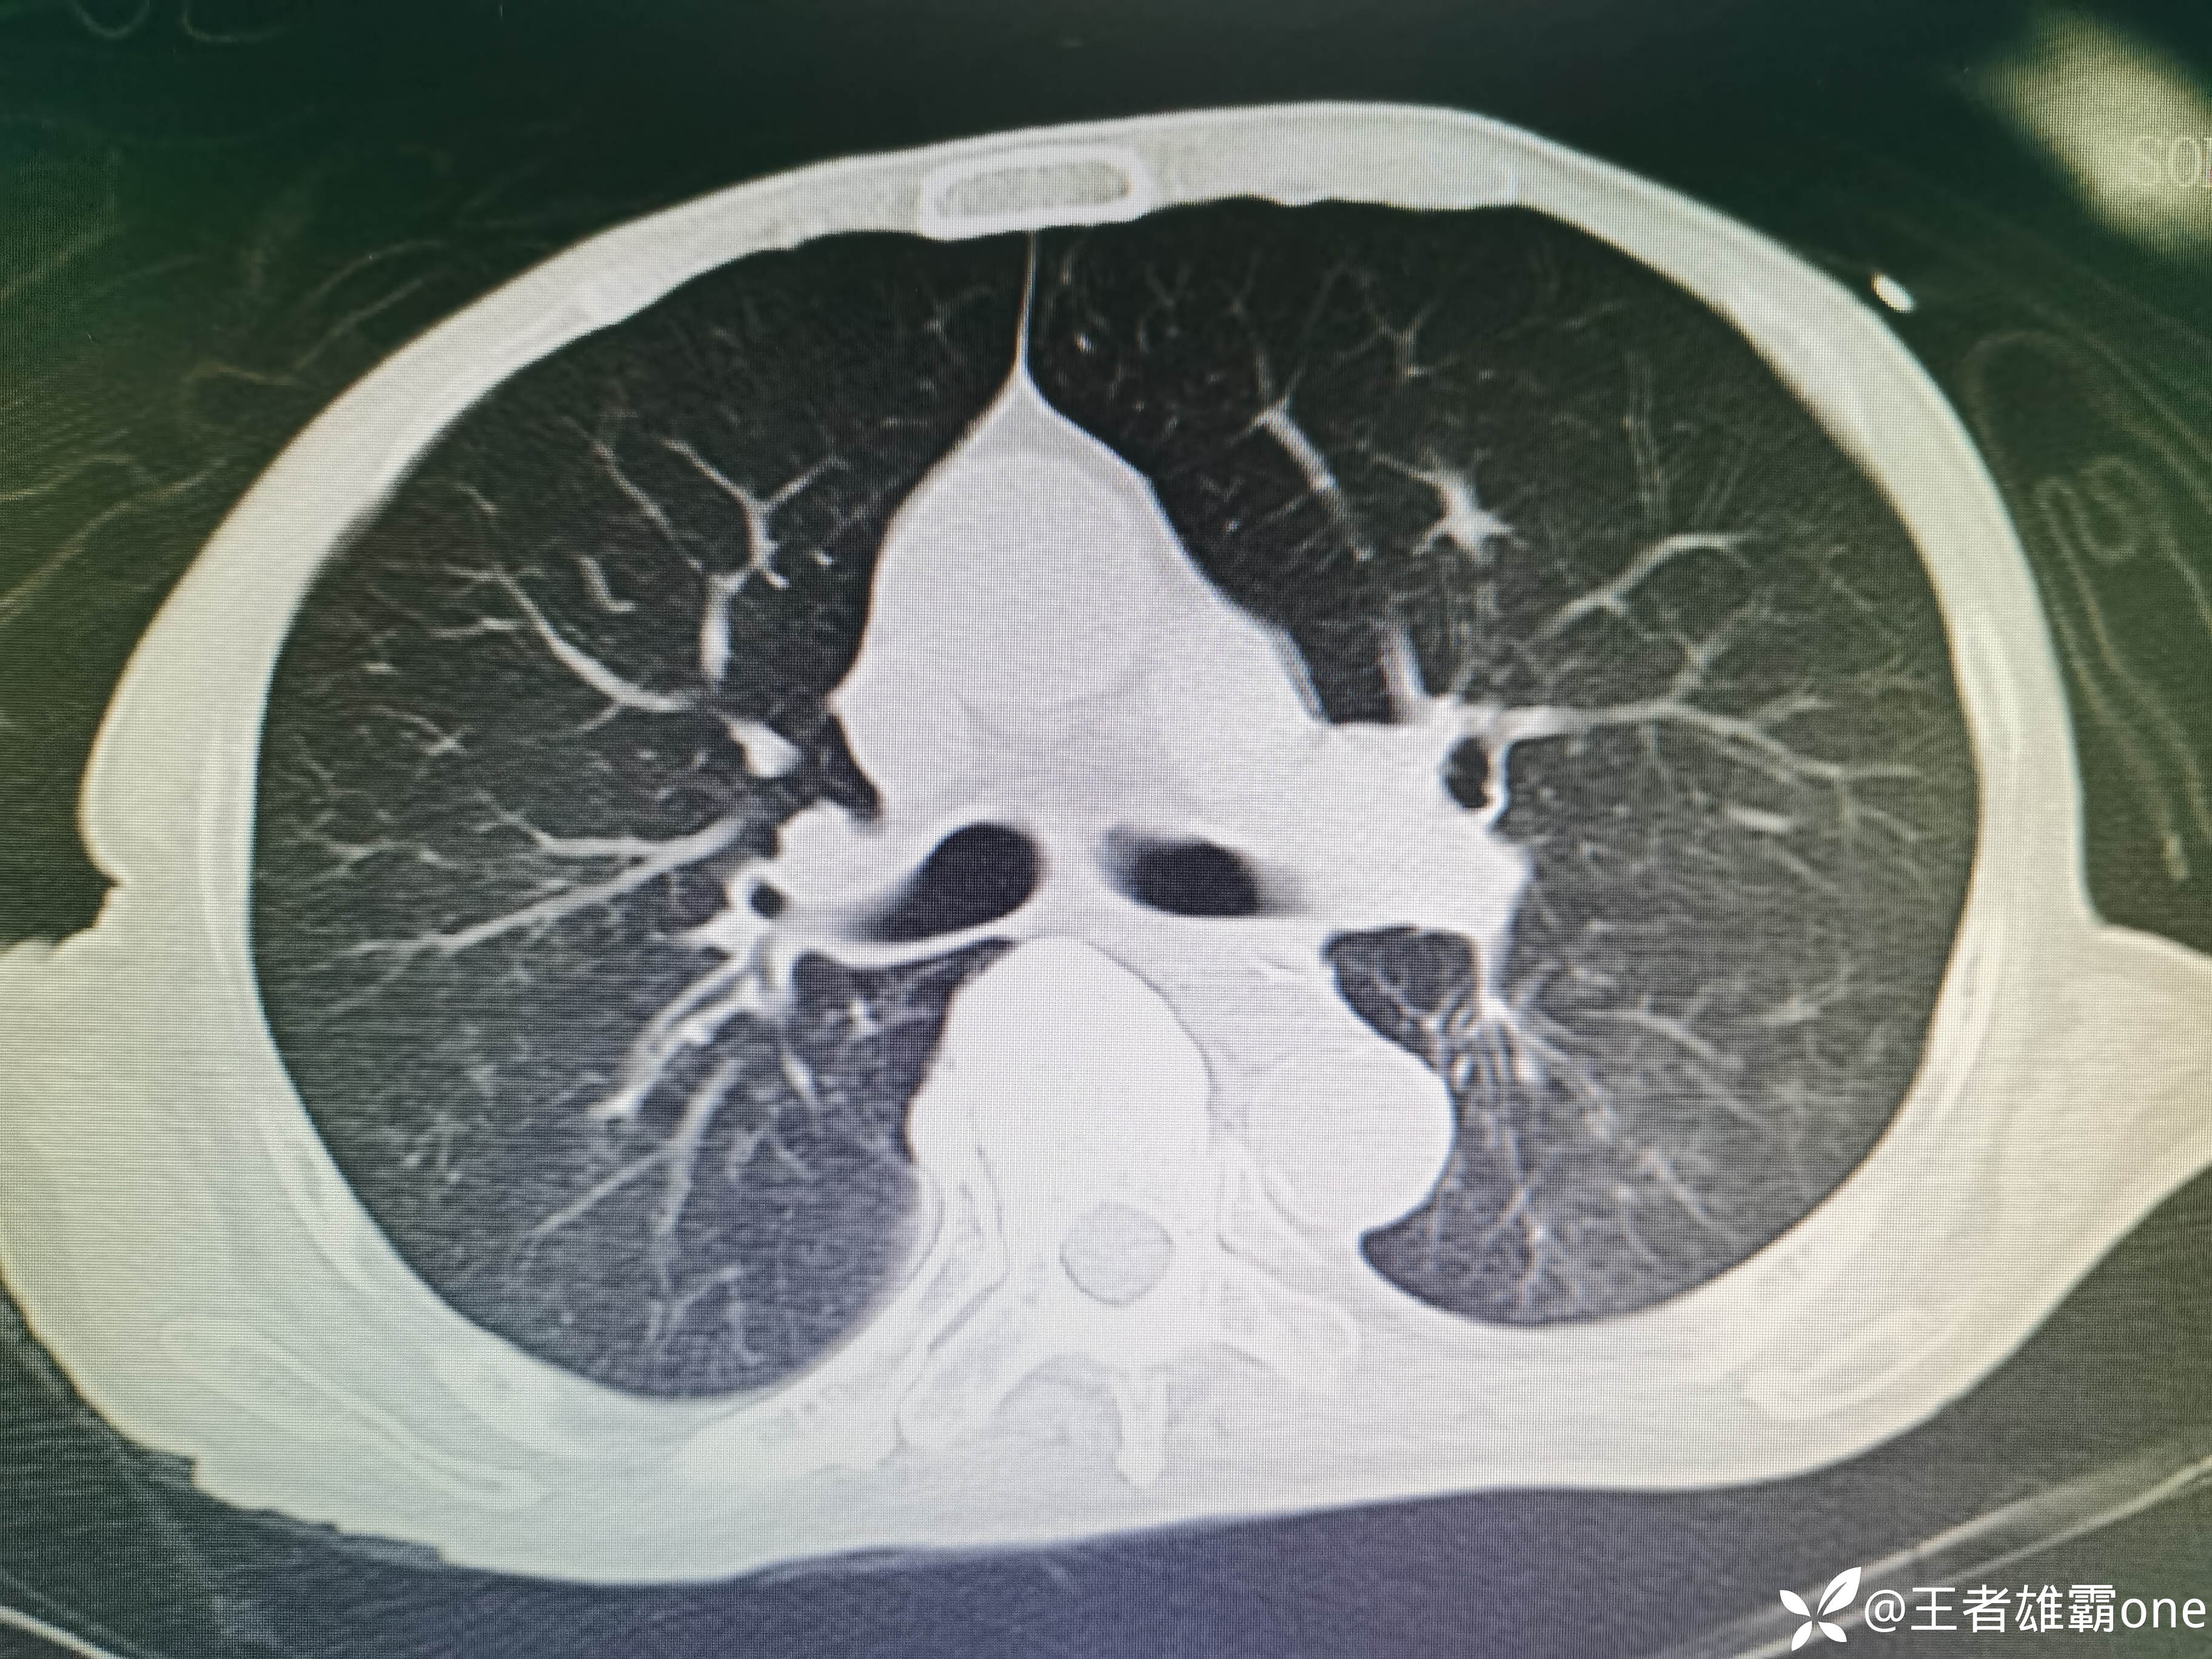

入院时胸部CT:

具体图片: